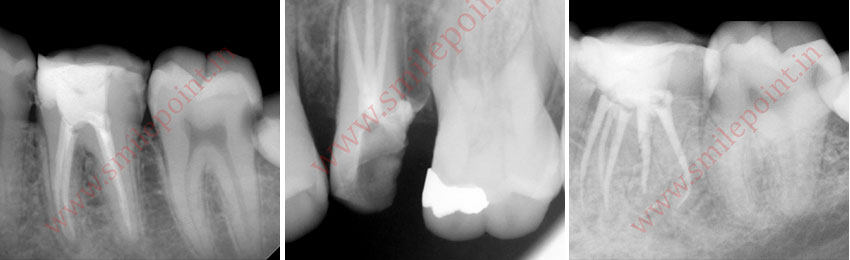

Computer assisted and navigated root canal treatment